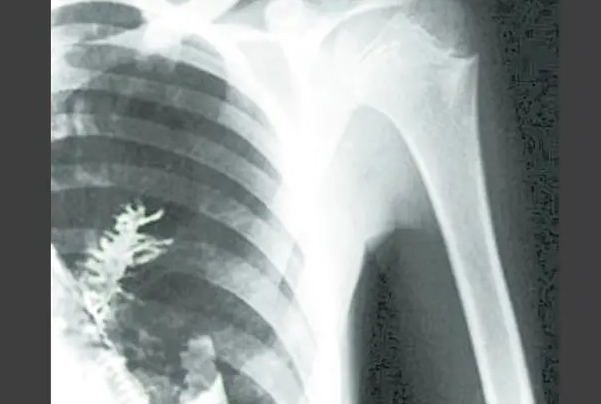

直到这种疼痛持续了一段时间之后才引发了他的重视 , 因为身体每况愈下 , 让他感觉到即便是普通的呼吸也会带有一定的刺激感 , 严重的时候甚至还出现咳血 , 这样的局面也证明他的身体的确出现了问题 。 因此他赶忙前往医院进行诊断 , 结果是让人难以接受的 , 因为这位自认为身体健康的人 , 发现自己是肺癌晚期 。

医生在为西多尔金进行手术的过程中发现一件让人惊讶的事情 , 因为在西多尔金的肺部出现了一棵冷杉树 。 医生凭借着自己高超的技术 , 冒着极大的风险 , 将这棵树取得出来 。 而这样的局面也证明 , 西多尔金其实肺部出现疼痛的问题 , 并非是因为他患上了肺癌 , 而是因为肺部所生长的这棵树木 , 让他出现严重的身体问题 , 以至于医生误判 。